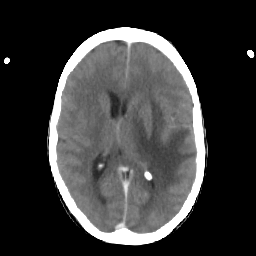

Metastatic bronchogenic carcinoma: Roentgen-ray CT -- Slice #12

[Home][Help][Clinical] Slice 12